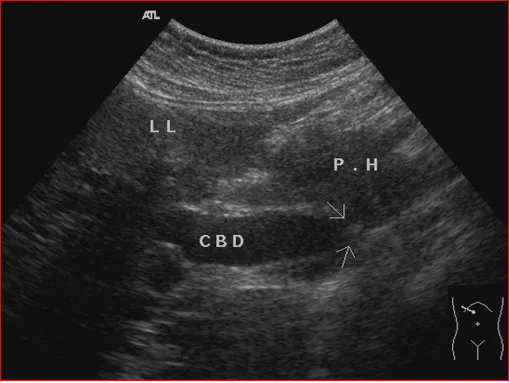

上腹部斜纵切显示胰头癌压迫胆总管

● 灰阶超声表现

1.直接征象

①小于2cm的肿瘤多为均匀低回声,圆形,与正常组织无明显界限,无包膜,后方回声衰减不明显

②随肿瘤增大肿块内回声不均匀,部分可有钙化、液化、或呈高回声改变,肿物边界不清,呈浸润性生长,形态不规则,后方回声衰减

④胰头癌胰管呈不同程度扩张,内壁平滑

2. 间接征象

①胆管扩张,胰腺头癌和肿大的淋巴结可浸润或压迫胆总管,引起胆道梗阻。超声可见扩张的胆总管中断于胰腺的低回声肿物内